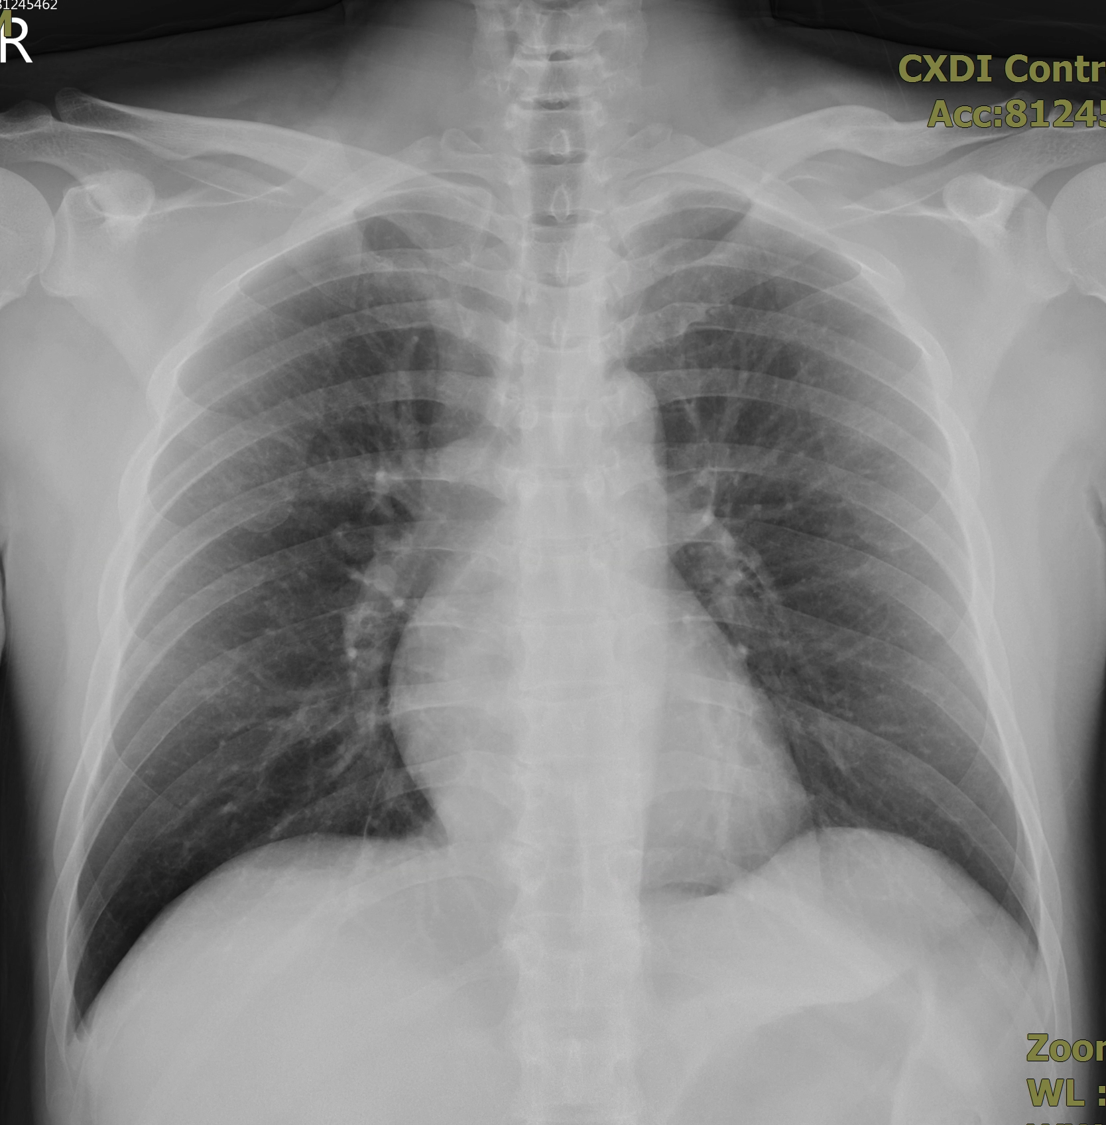

EKG showed no specific ST segment change. Cardiac enzyme was mildly elevation. Chest X ray showed no cardiomegaly or pulmonary edema.